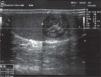

La ecografía testicular, realizada con transductor lineal de 12MHz, mostró una lesión hipoecogénica, de morfología redondeada, que presenta láminas hiperecogénicas concéntricas en su interior, asociada a microcalcificaciones, que mide 1,8×2,4cm de diámetros transversos, ubicado en el testículo derecho. En el testículo izquierdo se observó otra lesión hipoecogénica de morfología redondeada, que presenta halo de mayor hipoecogenicidad de 0,55cm de diámetro transverso mayor, con calcificaciones periféricas, que proyectan una discreta sombra acústica posterior.